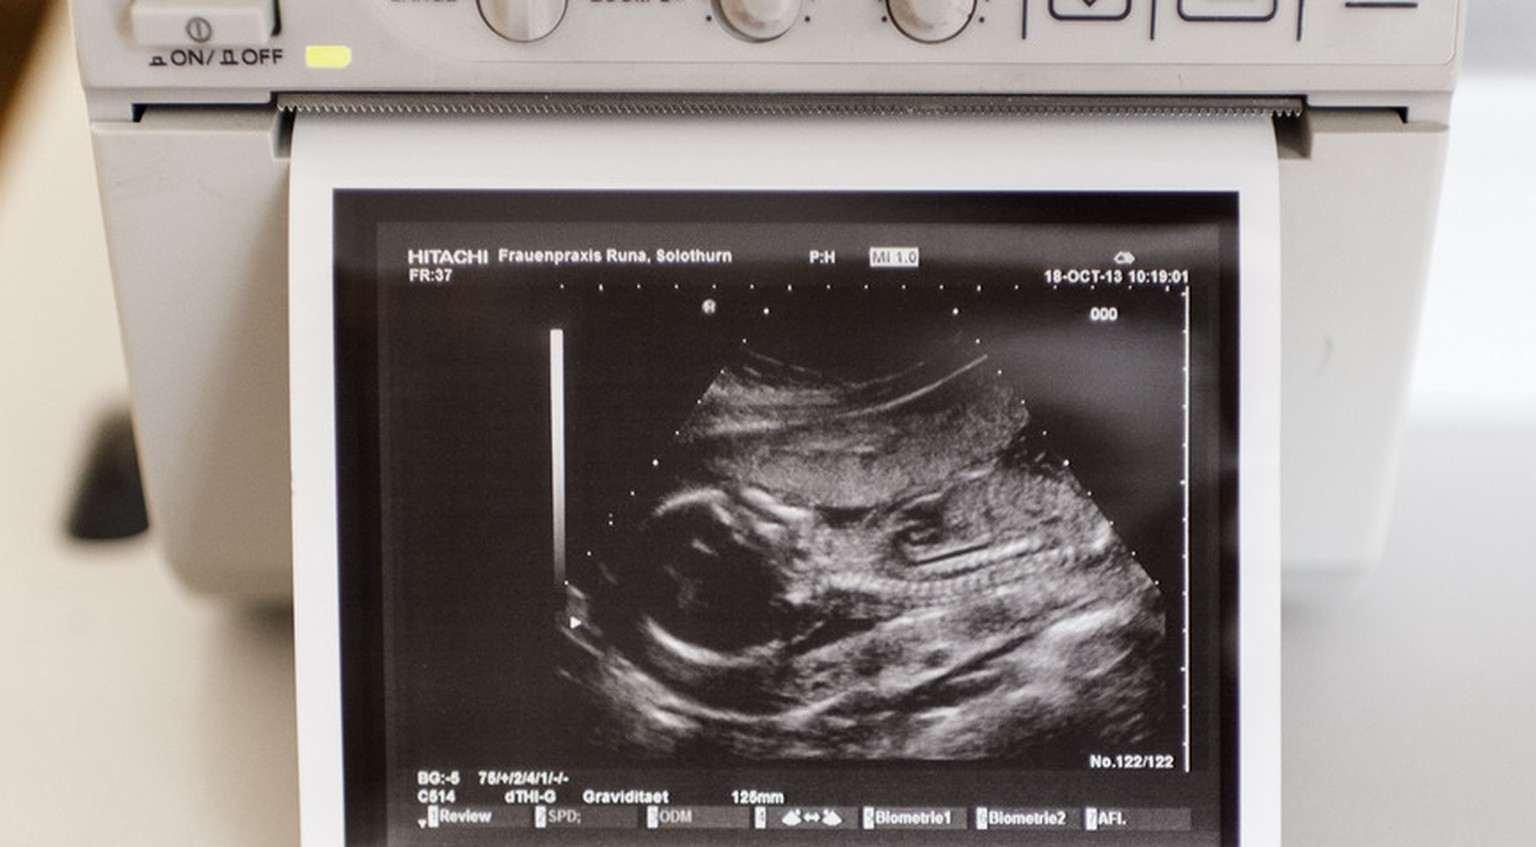

Sperma ja, Eizelle nein: Heute dürfen verheiratete Paare in der Schweiz auf eine Samenspende zurückgreifen, wenn der Mann unfruchtbar ist. Ist die Frau unfruchtbar, ist die Lage eine andere: Bringen weder Hormonbehandlungen noch In-Vitro-Befruchtungen (Zeugungen im Reagenzglas) eine erhoffte Schwangerschaft, bleibt nur die Eizellenspende.

Enttäuschungen, gesundheitliche Risiken, seelische Strapazen: Der Fortpflanzungstourismus zeigt, wie weit Paare bereit sind zu gehen, um sich ihren Kinderwunsch zu erfüllen. Und wie viele mittlerweile auf eine künstliche Befruchtung angewiesen sind. Laut Schätzungen leidet in der Schweiz jedes sechste Paar unter Fertilitätsproblemen.

Allein 2012 liessen sich über 6000 Frauen in über 10’000 Behandlungszyklen künstlich befruchten, wie die Zahlen des Bundesamtes für Statistik zeigen. Mehr als 2000 ausserhalb des Mutterleibs gezeugte Babys kamen zur Welt. Damit haben sich die Zahlen zur medizinisch unterstützten Fortpflanzung in der Schweiz in nur zehn Jahren verdoppelt.